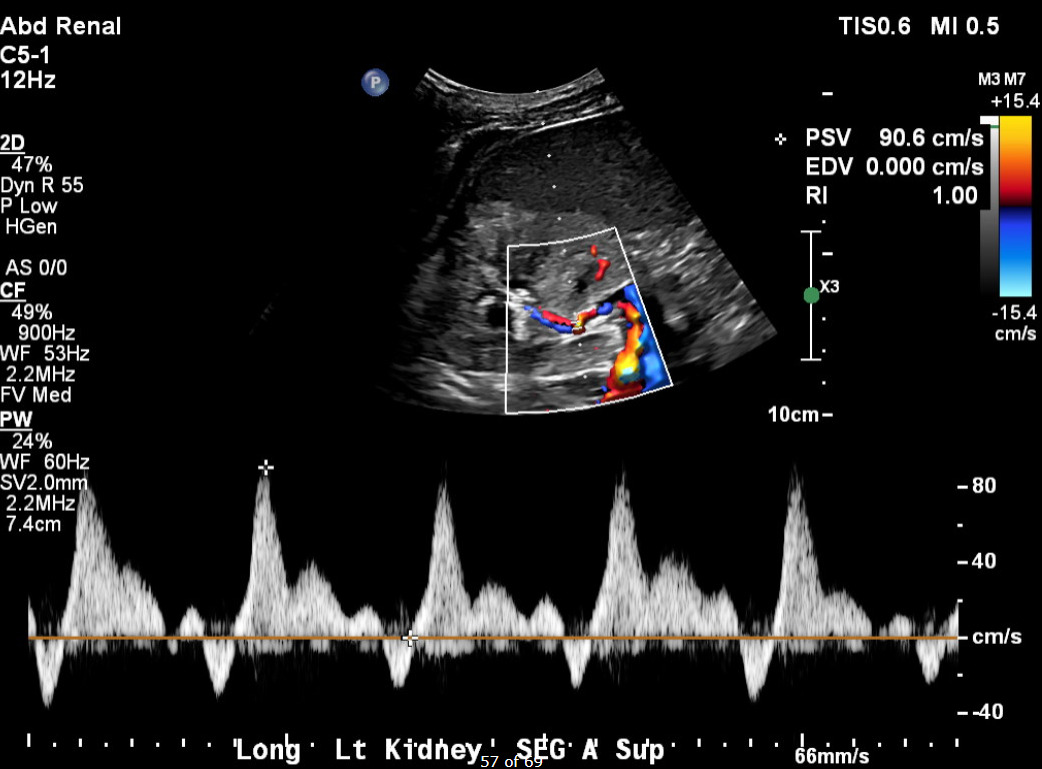

Her current presentation was characterized by a one-week history of worsening dyspnea, orthopnea, and paroxysmal nocturnal dyspnea. On arrival, her blood pressure was 257/169 mmHg, with tachypnea and bilateral inspiratory crackles on examination. Initial laboratory studies (Table 1) demonstrated serum creatinine 5.36 mg/dL, BUN 74 mg/dL, hemoglobin 8.2 g/dL, NT-proBNP >35,000 pg/mL, and high-sensitivity troponin T 93 ng/L, consistent with demand ischemia in the setting of hypertensive emergency. Urinalysis revealed 3+ proteinuria. Chest radiography demonstrated bilateral interstitial and alveolar opacities consistent with pulmonary vascular congestion. A transthoracic echocardiogram obtained during this admission demonstrated preserved LVEF (56–60%), severe concentric left ventricular hypertrophy, and grade I diastolic dysfunction. Renal duplex ultrasonography demonstrated bilaterally echogenic kidneys consistent with medical renal disease. Doppler interrogation of a segmental branch supplying the upper pole of the left kidney demonstrated elevated peak systolic velocity (~90.6 cm/s), absent end-diastolic flow (end-diastolic velocity 0.0 cm/s), and a markedly elevated resistive index (RI = 1.0) (Figure 1), findings which may suggest severe intrarenal hemodynamic compromise and a probable functionally significant focal upper-pole segmental renal artery stenosis. Flow velocities in the main renal arteries and other segmental branches were within normal limits (Figure 2). Computed tomographic angiography was not performed due to advanced renal dysfunction. Magnetic resonance angiography was also considered; however, it was not pursued during this hospitalization because additional imaging was unlikely to alter immediate management, particularly in the setting of advanced chronic kidney disease and the patient’s preference to avoid renal replacement therapy.

Several reports have demonstrated that unilateral renal artery stenosis may precipitate flash pulmonary edema when renal functional reserve is reduced, including cases involving contralateral kidney atrophy or solitary kidneys.4–6 These observations support the concept that loss of effective renal mass, rather than anatomic bilaterality alone, may reproduce the physiologic consequences traditionally attributed to bilateral disease. In our patient, advanced chronic kidney disease likely amplified the hemodynamic impact of the focal segmental lesion, allowing a localized vascular abnormality to produce recurrent systemic decompensation. Building on this, the case further emphasizes the importance of thorough renovascular evaluation, even when abnormalities appear subtle. Segmental or branch-level renal artery stenosis can be missed when diagnostic evaluation is limited to the main renal arteries, as Doppler criteria validated for main artery disease may not reliably identify focal branch involvement⁷. Seoung et al. showed that systematically comparing intrarenal Doppler waveforms across multiple renal segments (upper, mid, and lower poles), and noting significant regional hemodynamic differences, can suggest the presence of a hemodynamically important focal lesion.7 In this case, duplex ultrasonography demonstrated abnormal renal arterial hemodynamics confined to an upper-pole segmental branch (Figure 1), while waveforms in other intrarenal segments were preserved (Figure 2). This regional disparity may support the presence of focal segmental renovascular disease. This pattern has been reported as a cause of renovascular hypertension but remains susceptible to under recognition.7

Although computed tomographic angiography could not be performed because of advanced renal dysfunction, duplex Doppler ultrasonography remains a validated noninvasive tool for renovascular assessment. Intrarenal Doppler abnormalities, including absent or reversed end-diastolic flow and elevated resistive indices, have been described as surrogate indicators of hemodynamically significant renovascular disease when main renal artery velocities are normal; however, these findings represent indirect evidence and must be interpreted in conjunction with clinical features and renal functional reserve.8